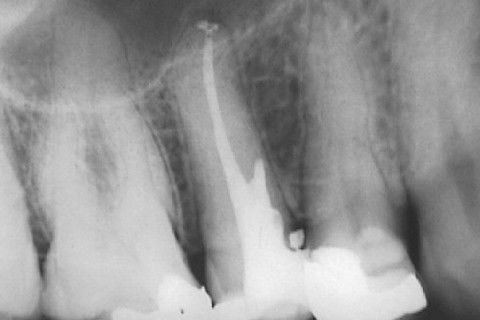

Calcificação Distrófica